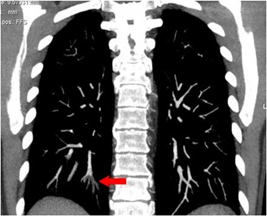

Những năm vừa qua được sự quan tâm của thủ trưởng các cấp cùng với sự đầu tư của Đảng ủy, Ban giám đốc Bệnh viện trong chẩn đoán và điều trị, bệnh viện đã trang bị nhiều máy móc hiện đại, trong đó đặc biệt có máy CT Scanner 16 Slice SIEMENS của Cộng Hòa Liên Bang Đức, cùng với sự chuyển giao kỹ thuật, công nghệ mới, các bác sỹ và kỹ thuật viên đã làm chủ hoàn toàn các kỹ thuật phức tạp mà chỉ có tuyến tỉnh và trung ương mới đáp ứng được như: Chụp CTscanner có thuốc cản quang gan ba thì, ổ bụng, lồng ngực, sọ não, hệ mạch máu bụng, chậu, chi…Trong thu dung cấp cứu, máy CT Scanner càng phát huy thế mạnh trong chẩn đoán chấn thương sọ não, chấn thương bụng kín…